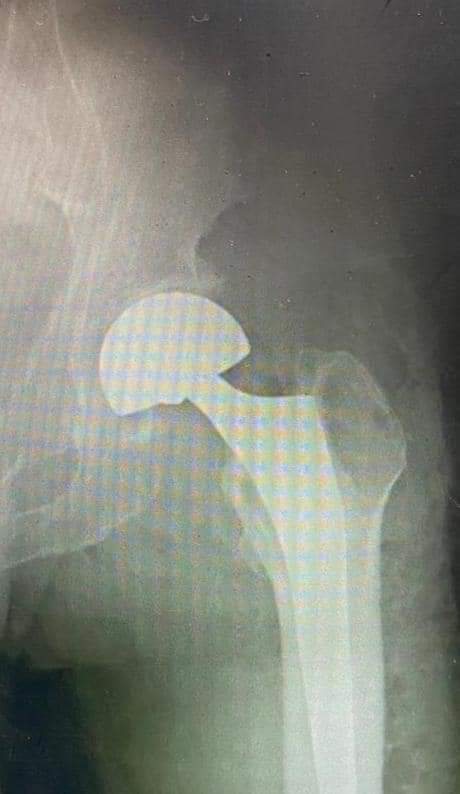

وطنا اليوم -  يقوم بعمليات تثبيت الكسور المعقدة بشكل طاريء وتبديل المفاصل بشكل مبرمج  مما خفف على المواطنين البحث عن أسرة في مستشفيات مركزية رغم صعوبة عمليات العظام من الناحية التقنية في المستشفيات النائية  إضافة الى  استقبال اعداد كبيرة بالعيادات ومعالجة جميع المرضى بالطرق المثلى انه الدكتور الانسان البارع والمتميز يزيد البريزات طبيب العظام في مستشفى الاميرة سلمى / ذيبان عيادة العظام  علماً بأنه كان  مستشفى تحويلي منذ تاسيسه والدكتور البربزات وقبل اربع سنوات في عام 2020  منذ انتقاله للمستشفى يقوم بهذه العمليات ومن بينها  عمليات نوعية لمرضى يعانون من كسور معقدة في الترقوة واجراء عمليات دقيقة ومعقدة لكسور لمرضى في مختلف أنحاء الجسم وعمليات تثبيت الكسور المعقدة وتركيب المفاصل وغيرها الكثير  والديسك " وآلامه وتبعاته وعلاجه وإجراء عمليات معقده وصعبه.

وأجرى الدكتور البريزات عمليات كبرى في جراحة العظام والتي تحتاج إلى مراكز متقدمة ومتطورة. وكذلك العمل على تثبيت أغلب انواع الكسور بطريقة طارئة وتبديل المفاصل بطريقة مبرمجة بما يتناسب مع امكانات المستشفى والتي هي  جزء من  العمليات الدورية بمستشفى الاميرة سلمى في ذيبان  والتي تخفف العبئ على المستشفيات المركزية وعلى المواطن في آن واحد.

وعبر كثير من  المرضى وذويهم عن عظيم شكر هم وامتنانهم للدكتور البريزات على ما بذله ويبذله  من جهود كبيرة واستثنائية في تعامله مع المرضى والمراجعين  ومتابعته الحثيثة لهم والاطمئنان عليهم والتي تكللت جميعها بالنجاح وله الدور الكبير   برفع كفاءة قسم العظام  بالمستشفى بشكل عام والذي  أصبح  متطوراً بالقيام بالعمليات مثل تثبيت الكسور المعقدة و تركيب المفاصل و غيرها.